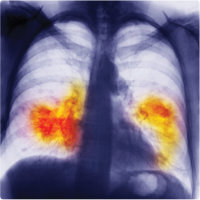

MT Feb 2013 Chest X-ray showing lung cancer

Viruses could help control certain fast-growing lung cancer cells, according to researchers at Johns Hopkins University. In recent years, Seneca Valley virus – which selectively targets cancerous cells but not normal somatic cells – has shown promise as a potential anti-cancer treatment. However, some types of aggressive ‘small cell lung cancer’ have previously been thought to be resistant to infection. By manipulating the viral genome to produce a green fluorescent ‘reporter’ protein, the researchers found that a small sub-population of these cancer cells is in fact highly susceptible to the virus. The researchers also confirmed that only cancerous cells were targeted: when they infected tumour-bearing mice with the virus, it did not replicate in normal tissues. The ability to infect only a subset of tumour cells could prove useful in anti-cancer treatments. For example, viruses could be used to deliver toxins to specific cancer-affected regions of the body.

Figure: Chest X-ray showing lung cancer. Photodisc / Thinkstock